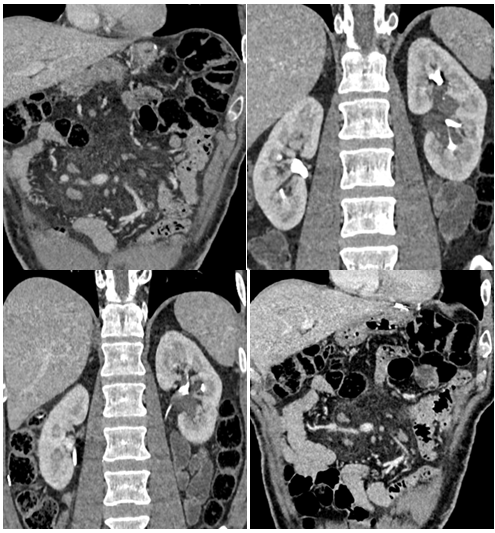

Again appears as left mild hydro nephrosis without stone and hydro ureter. CT urogram performed and reveals no hydro nephrosis. No stone in kidneys, ureters and urinary bladder. Re-demonstration of cystic structures from left renal pelvis extending alongside of non-dilated pelvi calyceal system. Incidentally noted mesenteric root fat stranding with multiple lymph nodes, representing mesenteric panniculitis.1–3

Figure 2 Axial Images: CT urogram was advised to exclude stone. CT urogram shows no hydro nephrosis. No stone in kidneys, ureters and urinary bladder. Re-demonstration of cystic structures from left renal pelvis extending alongside of calyceal system. Incidentally noted mesenteric root fat stranding with multiple lymph nodes, representing mesenteric panniculitis.

Figure 3Axial Images: CT urogram was advised to exclude stone. CT urogram shows no hydro nephrosis. No stone in kidneys, ureters and urinary bladder. Re-demonstration of cystic structures from left renal pelvis extending alongside of non-dilated calyceal system. Incidentally noted mesenteric root fat stranding with multiple lymph nodes, representing mesenteric panniculitis. Non-contrast study for comparison.

Figure 4 Coronal reconstruction: for better depiction of cystic structures in left renal pelvis extending alongside of calyceal system with no hydro nephrosis . Contrast filled pelvicalyceal system and renal pelvis appears unremarkable.